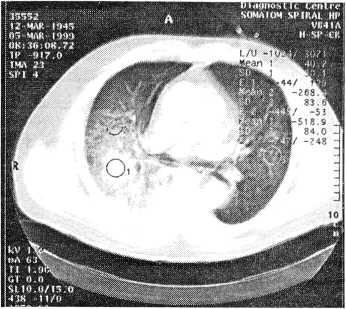

РКТ от 07.03.99 г. (рис. 2): сохраняется неоднородная инфильтрация легочной ткани в проекции S, — S2, S6 и базальных сегментов, обусловленная наличием мелких очажков деструкции либо образованием эмфизематозных булл в зоне инфильтрации. Гиповентиляция S6 и S9 — S10 справа. Небольшие участки инфильтрации в проекции язычковых сегментов и S8 слева. Трахея и главные бронхи видны до сегментарного уровня. Увеличены паратрахеальные и параортальные лимфоузлы и имеет место умеренное количество выпота в плевральных полостях и в перикарде. По РКТ достоверных признаков деструктивного процесса нет.

Рис. 2. Компьютерная томограмма больного В. в ходе лечения